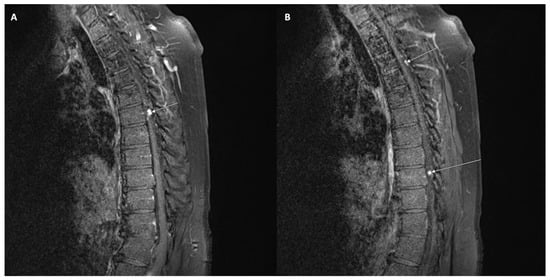

Spinal seeding metastasis has also been observed in oligodendrogliomas. These tumors are associated with recurrence and lethal outcomes. Drop metastasis is seen in 1–2% of all cases. This phenomenon is depicted in Figure 5. There is no information on how this occurs, and blood and lymphatic metastasis are proposed mechanisms. The time to metastasis has been reported to be anywhere between 3 months and 6 years. Metastasis has been associated with a higher histopathological grade, although seeding can occur without malignant transformation. Following decompression surgery, this patient was managed with chemoradiotherapy [106]. Another case report describes a similar patient with spinal metastasis following resection of a low-grade frontal oligodendroglioma. In this case, surgical resection allowed for an overall survival of 1 year after the initial diagnosis. Spinal metastasis was found to occur years after resection of the primary tumor in this case, and spinal seeding was demonstrated to be a negative event indicating short survival [107].

Figure 5.

T1-weighted contrast-enhanced MRI demonstrating drop metastases at T6 (A), T3, and T9 (B) in a patient who previously underwent a resection for an ependymoma.